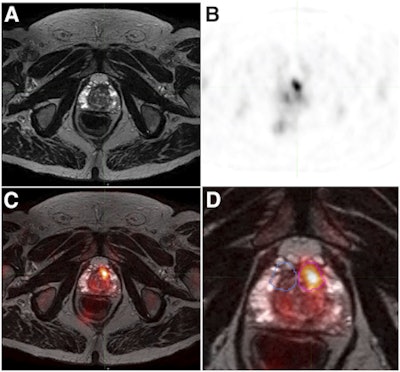

T2-weighted fast spin-echo MRI (A), F-18 choline PET (B), and fused PET/MRI (C) show a 0.68-cm3 left anterior transitional zone lesion that was confirmed on targeted biopsy. A magnified view of PET/MRI (D) shows a target lesion (magenta) and respective mirrored (blue) background volumes of interest. Image courtesy of JNM.A total of 52 lesions were detected by multiparametric MRI (19 low, 18 intermediate, and 15 high-risk), and mpMRI-assigned risk was a strong predictor of final pathology (area under the curve [AUC] = 0.81, p < 0.001).

Using the mean F-18 choline target-to-background ratio, the addition of F-18 choline to mpMRI significantly improved the prediction of significant cancers, compared with mpMRI alone (AUC = 0.92, p < 0.001).